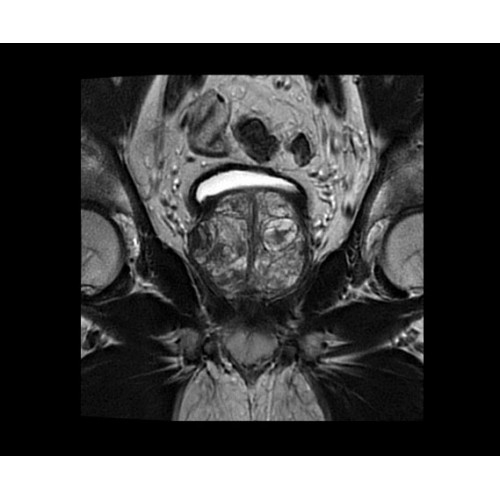

• BodyWorks — для визуализации абдоминальной и тазовой областей, подстраиваясь под запросы пользователя с учетом любых типов пациентов.

Поле обзора 50x50x50 см и апертура шириной 70 см позволят достоверно визуализировать сложные анатомические области для пациентов с крупным телосложением, например, плечи и бедра. Феноменальная однородность системы SIGNA Architect обеспечивает наиболее широкое поле обзора с улучшенными характеристиками градиентов. Ничто не останется незамеченным.